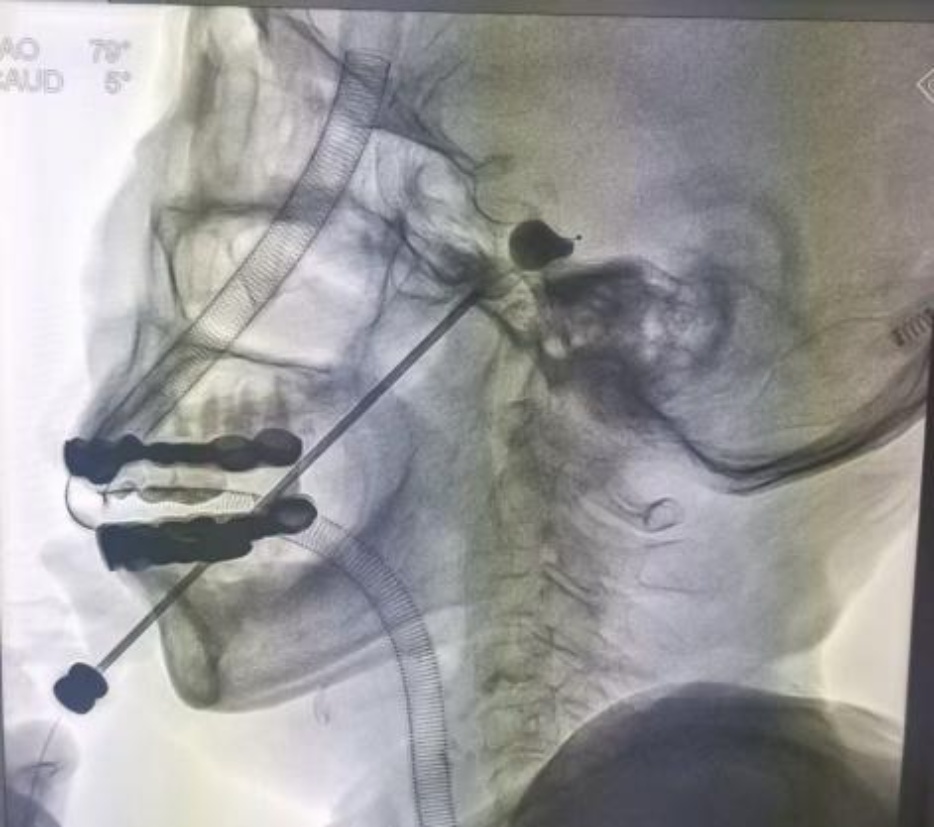

为动态评估两组患者术后无痛生存时间,本实验绘制了Kaplan-Meier生存曲线,见图1。结果显示,维持初压组的累积无痛生存率曲线显著高于非维持初压组,疼痛复发时间更晚、累积无痛生存率更高(Log-rank χ2 = 4.281, P = 0.039)。术后12个月时,维持初压组的累积无痛生存率为95.9%,非维持初压组为84.2%;随着随访时间延长至24个月,两组累积无痛生存率分别为91.8%和77.2%,组间差异随时间推移呈逐渐扩大趋势。

Figure 1. Kaplan-Meier survival analysis

1. Kaplan-Meier生存分析